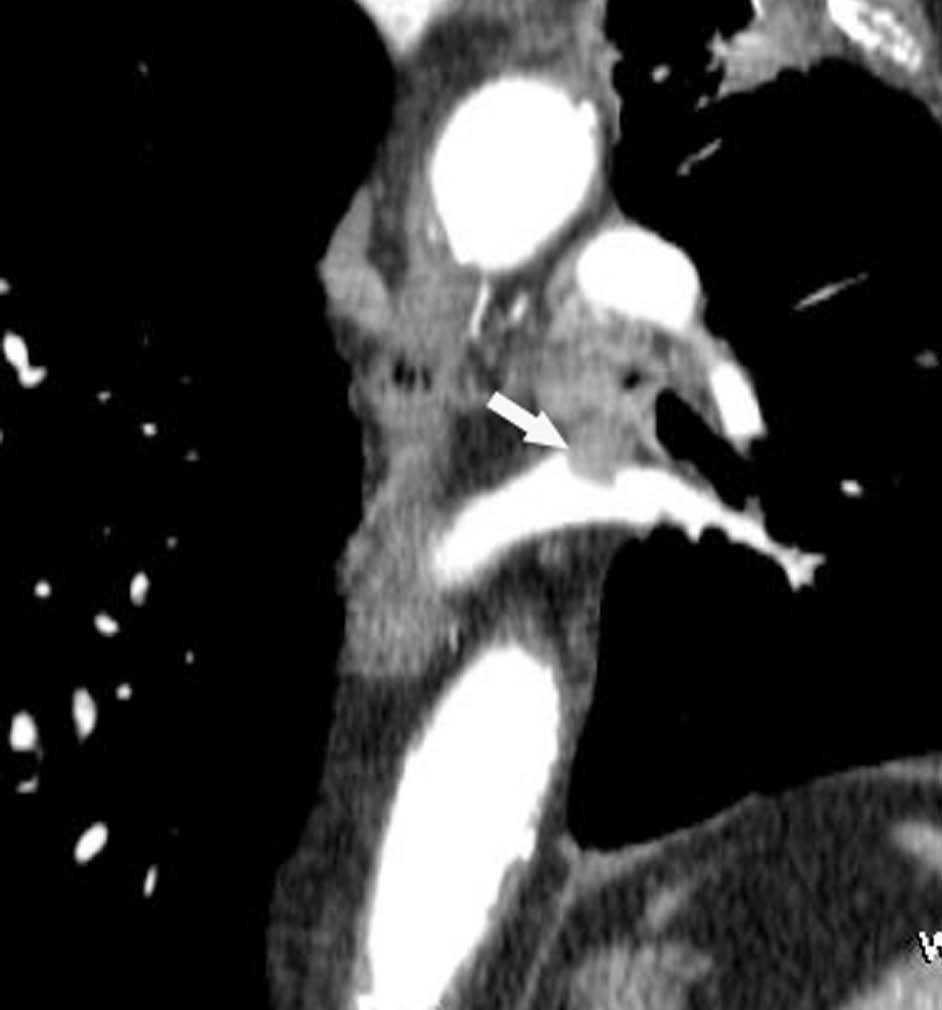

Fig. 2.--T4. (A) Corte axial de tomografía computarizada (TC) torácica con contraste. Tumor hiliar derecho que infiltra la arteria pulmonar derecha, la vena cava superior y engloba al bronquio intermediario. (B) Reconstrucción coronal oblicua, longitudinal al eje de la arteria pulmonar derecha, que muestra cómo engloba el tumor a la rama del truncus superior (flecha blanca) e inferior (flecha negra).